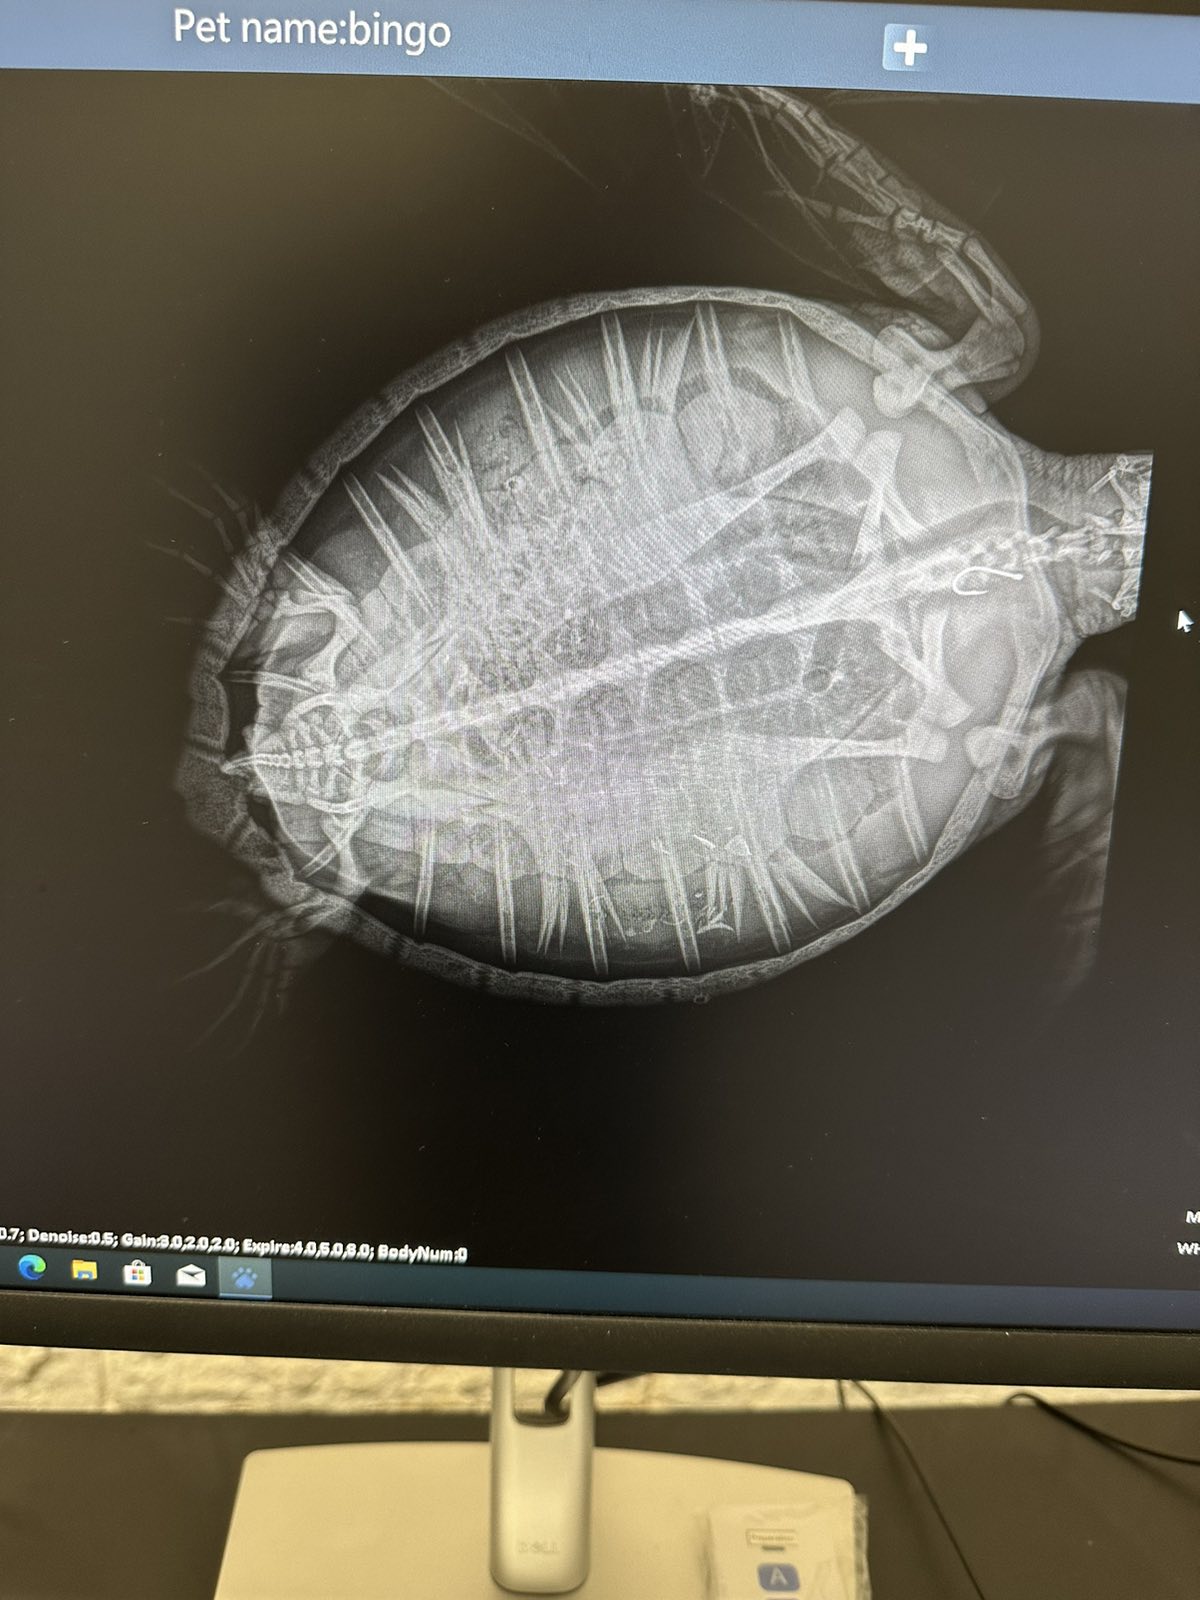

Jedinka je pronađena u okolici Crikvenice, a nažalost, progutala je ribarsku udicu s najlonom. Rendgenskom snimkom potvrđena je pozicija udice koja će biti uklonjena, objasnili su iz Centra.